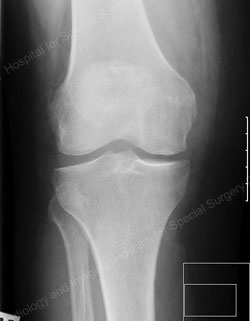

Figure: Example of a fixed bearing unicondylar knee replacement

(the images on top represent a preoperative joint; the images on the bottom represent a postoperative joint)